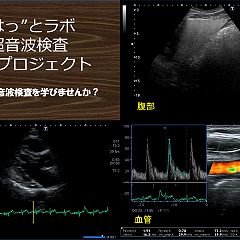

フォロー ブログを報告 登録ID 2031944 タイトル ハットラボ 山陰で生きる臨床検査技師の初のウェブサイト URL https://hattolaboblog.com/ カテゴリ 生活・文化(全般) (601位/2,674人中) 社会・経済(全般) (315位/1,184人中) 人間関係 (184位/418人中) 臨床検査 (5位/15人中) 日々の出来事 (1278位/2,975人中) 紹介文 「臨床検査技師」の服部博明と申します! 臨床検査技師ってご存知ですか?検査情報だけでなく時事ネタに関すること趣味に関すること私の人生に関することなどなど雑多なブログです。 登録:2020年02月(6年) 3 記事一覧